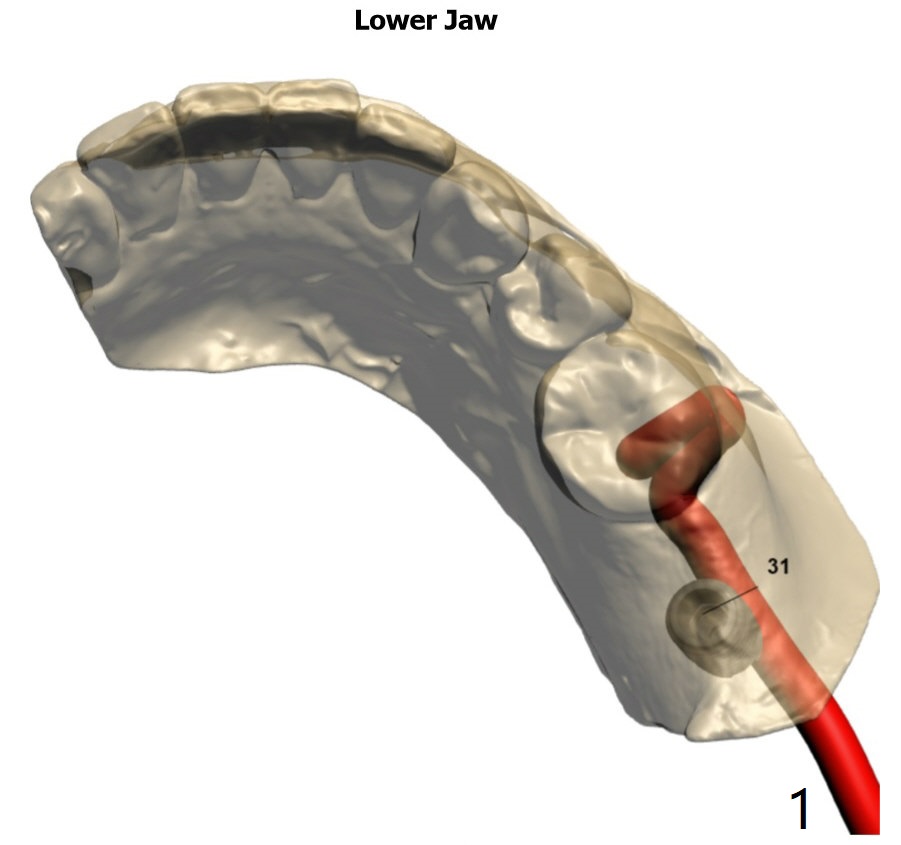

Seven months post socket preservation. Due to coronavirus, the surgery is postponed for 3 months. When the patient returns, take a PA for density check using sensor I. Also take a PA for #3 implant. Take 5x5 pre- (crestal cortex formation? (10 months post socket preservation)) and post-op.